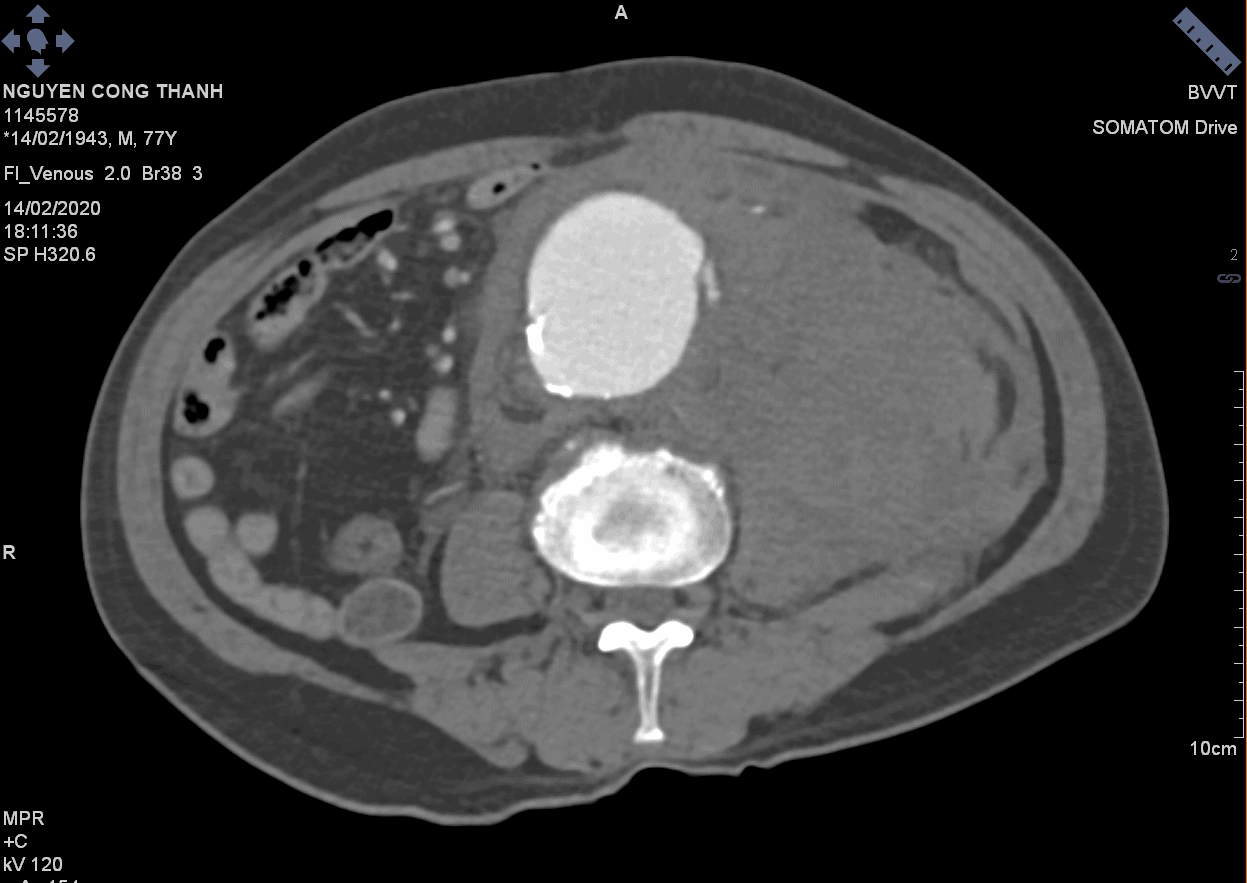

Vỡ phình ĐM chủ bụng

Vỡ phình ĐM chủ bụng - Ảnh 3

» Thông tin: Nam giới – 77 tuổi.

» Lâm sàng: Đau bụng cấp.